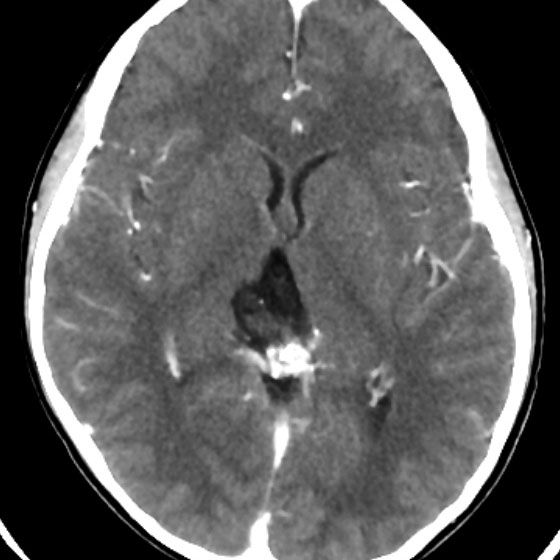

手術後のMRI

手術後にガドリニウム増強MRIで脳脊髄播種がないかどうかの確認をしました。腫瘍は全摘出できていて,複視や視野障害などもなく無症状です。